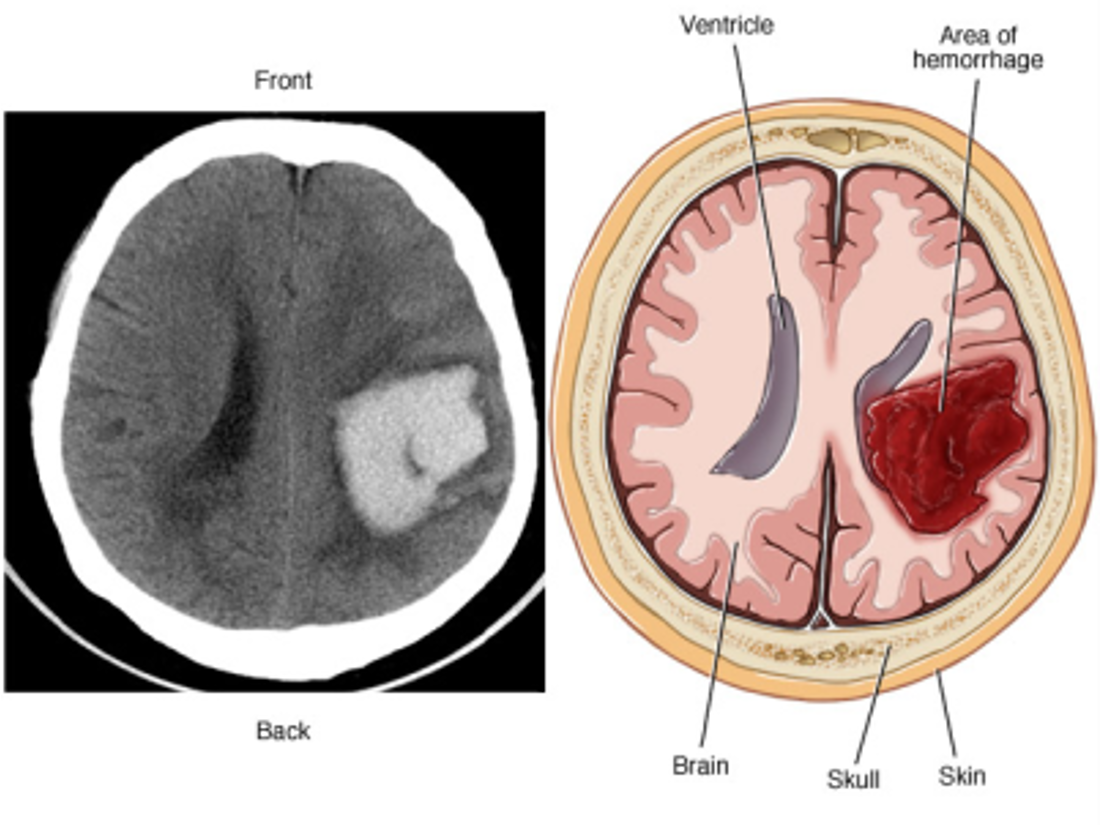

Define the types of stroke - hemorrhagic

• Hemorrhagic

• Intracerebral

• Bleeding within brain caused by rupture of a vessel

• Sudden onset of symptoms

• Progression over minutes to hours because of ongoing bleeding

• Prognosis is poor with a 30-day mortality rate of 40-80%.

• Subarachnoid

• Bleeding into cerebrospinal fluid–filled space between the arachnoid and pia mater

• Commonly caused by rupture of a cerebral aneurysm, trauma, or drug abuse, arteriovenous malformation (AVM)

• Aneurysms silent killer -40% die during the first episode

• Brain bleed

• Non-contrast CT scan or MRI:

• Indicate the size and location of the lesion

• Differentiate between ischemic and hemorrhagic stroke